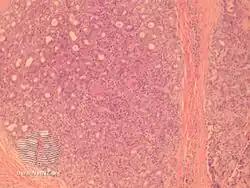

Aggressive digital papillary adenocarcinoma-pathology